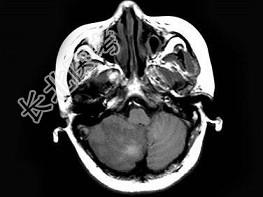

- 单项选择题女,58岁, 突发走路不稳1天,MRI检查见右小脑半球异常信号, 最可能的诊断为 ( )

A、脑梗死

B、病毒性脑炎

C、脑出血

D、星形细胞瘤

E、未见异常